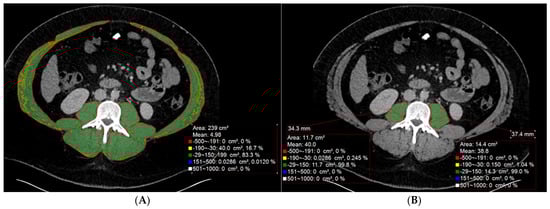

Sarcopenia, the loss of skeletal muscle mass and function, is a common and critical comorbidity in patients with conditions frequently managed by interventional radiologists, such as liver cirrhosis and hepatocellular carcinoma (HCC). Interventional radiologists are well positioned to incorporate opportunistic screening for this condition during routine preprocedural cross-sectional imaging. This review summarizes the current evidence on how sarcopenia influences patient outcomes and informs procedural planning across a spectrum of interventional radiology (IR) procedures. In transarterial embolizations for HCC, sarcopenia is a robust independent predictor of increased mortality, with meta-analyses suggesting it may also predict a lower tumor response rate. Even earlier stages of muscle loss (pre-sarcopenia) are associated with worse survival, and dynamic changes in muscle mass post-treatment can serve as a biomarker for tumor progression. For patients undergoing transjugular intrahepatic portosystemic shunt, pre-procedural sarcopenia and myosteatosis are strong, independent predictors of both mortality and the development of post-procedural hepatic encephalopathy, with the presence of both conferring the highest risk. In the context of pre-surgical portal vein embolization, sarcopenia is consistently associated with impaired volumetric liver growth, although this does not always translate to worse short-term surgical outcomes, as functional liver regeneration may be preserved. Following percutaneous liver tumor ablation, sarcopenia is a powerful predictor of overall mortality, while its role in predicting tumor recurrence remains an area of active investigation. Finally, in non-oncologic interventions for peripheral arterial disease, sarcopenia is highly prevalent and is associated with worse functional status, higher mortality, and a significantly increased risk of major amputation after endovascular therapy. In conclusion, sarcopenia is a powerful and readily available biomarker that provides crucial prognostic information—often independent of standard clinical scores—across a wide spectrum of IR procedures. The consistent evidence supports integrating sarcopenia evaluation into routine practice to enhance risk stratification, improve patient counseling, and guide multidisciplinary treatment planning. Full article